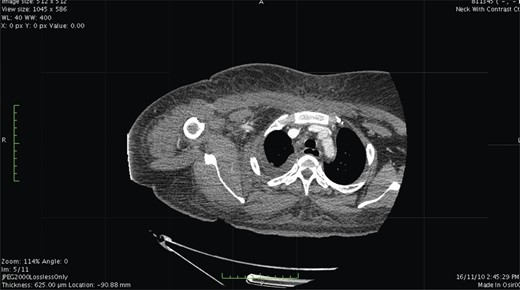

Contrast-enhanced computed tomography (CT) scan showed extensive cellulitis and thrombosis of the internal jugular vein and marked necrosis of the underlying muscles (Figs 1 and 2). The basic investigations revealed a haemoglobin level of 7.5 g/dl, a random plasma glucose level of 227 mg/dl and the fasting glucose level was 240 mg/dl.

Contrast-enhanced CT. At the level of base of skull shows airway luminal narrowing.